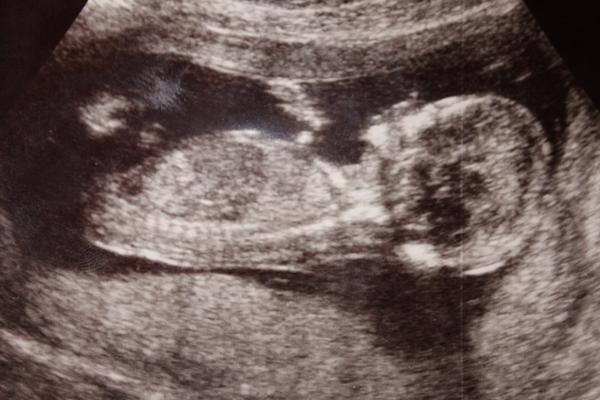

Ahoj, já jsem 13+1tt, Na Veveří v Brně mi na screeningu potvrdili na 90% kluka. Pozná se to prý podle pohlavního hrbolku - podle Dr. klukům vrcholek hrbolku míří víc nahoru k bříšku a holky ho mají protáhlejší směrem dolů k nožkám...Uvidíme, co nám potvrdí příště 🙂 ale já věřila, že je to bude kluk už od oné noci 😀 poprosila jsem o něj 😀 a to překvápko, když mi to potvrdili 😀 MUDr. Doubková umí vše krásně vysvětlit, je precizní a velmi příjemná... 😉

Ahojky, holky, kdyz zkoumali co cekate, tak to bylo asi podrobneji a priblizovali mimise? Mi v patek po dotazu, jedtli jse poznat, mimuse mela z boku celeho a pry ze kluk, byl ta videt jakoby pytlik, ale pochybuju, ze na konci 13 tt by tam byl a tak veliky, spis mi to prislo jako pup. snura.. :( uvidim ve stredu na kontrole, se poptam...